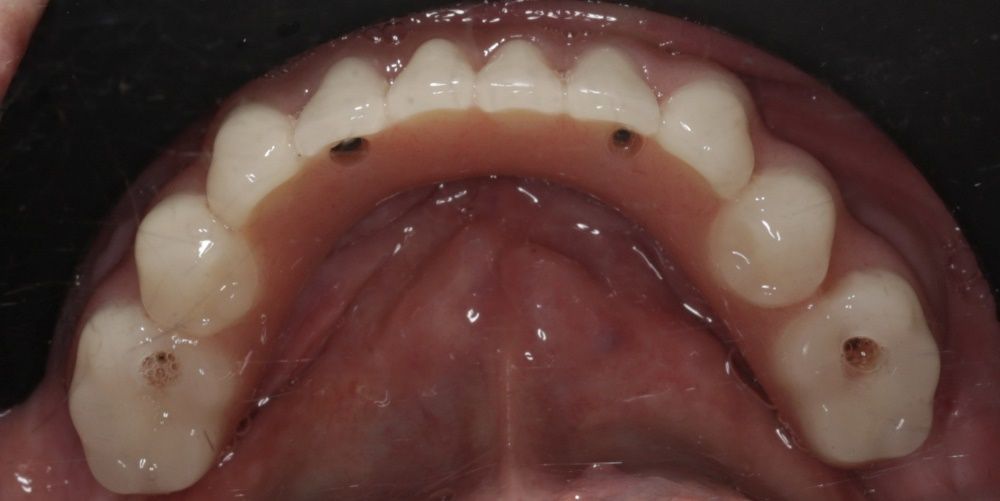

Имплантация жевательных зубов,

это самая востребованная операция.

Анна Анатольевна Кушнарева

хирург - имплантолог

фото коронок